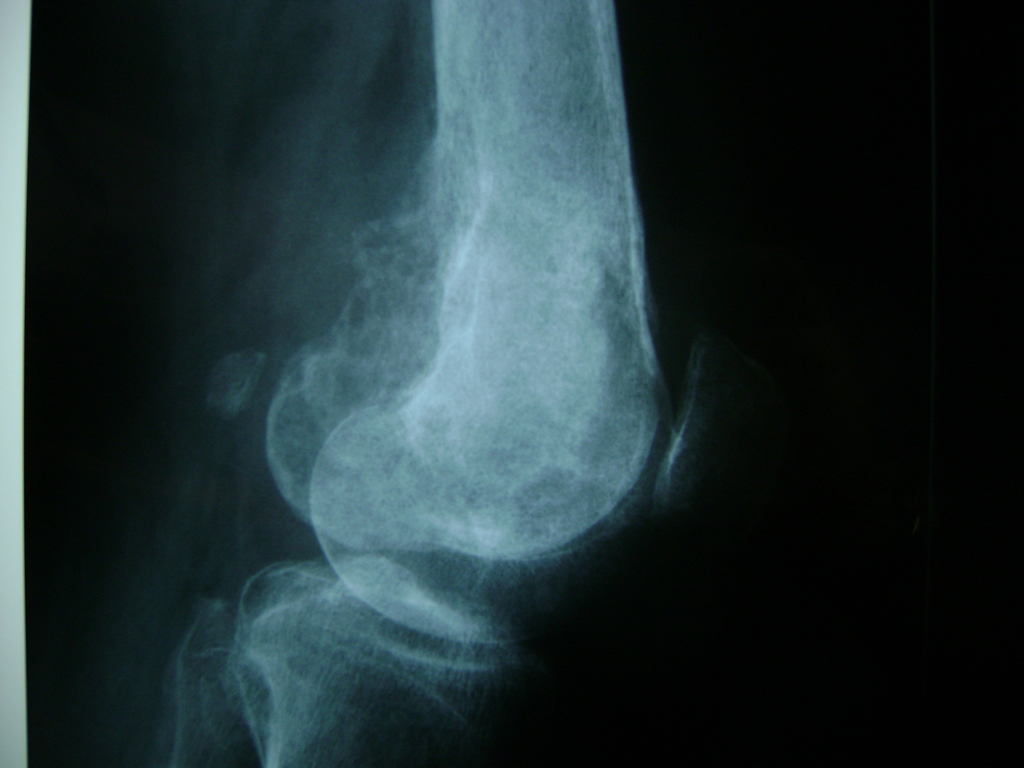

La artroscopia de rodilla es un cirugía en el cual la estructura interna de la articulación es examinada ya sea para realizar un diagnostico o para realizar un tratamiento, este procedimiento se realiza utilizando un instrumento parecido a un pequeño tubo llamado artroscopio.